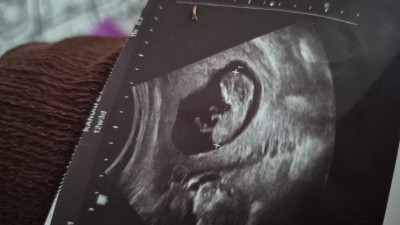

Kizlar sizce bu bebegin cinsiyeti nedir çok merak ediyorum doktor gördü ama söylemedi

Gebelik haftası 12+5

Doktorun gorup soylememesi tuhaf degil mi. Kiz bence

Daha erken dedi yanıltmamak için sanırım:)

Bencede kız